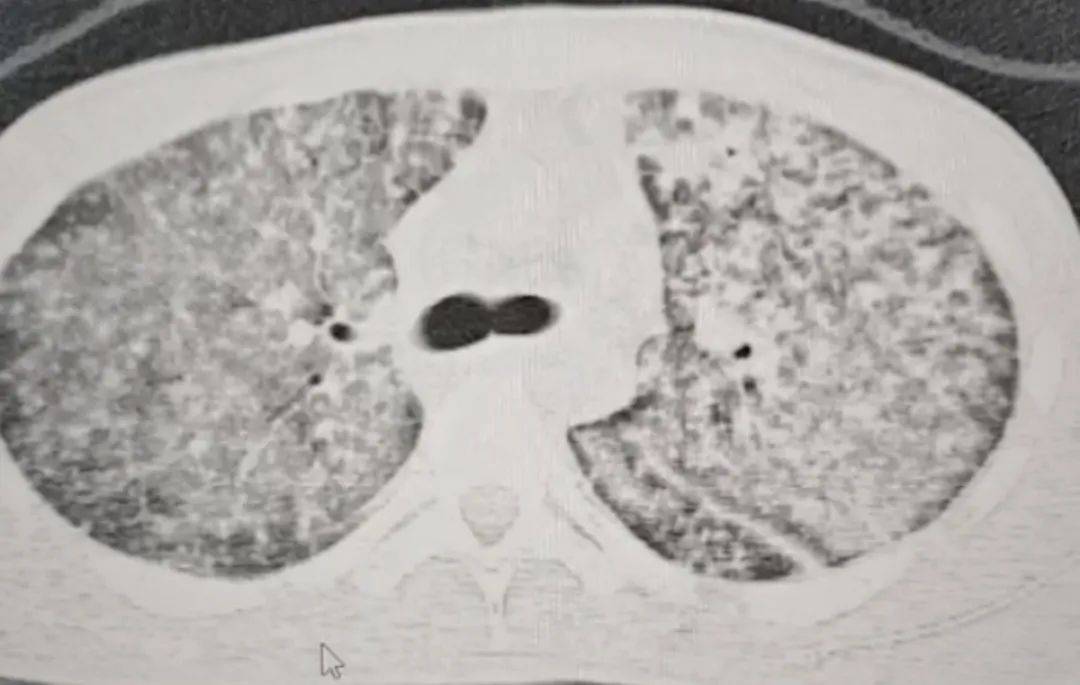

检查结果令医生大为震惊皇冠信用网开户 。肺部 CT 影像显示,小王的肺部几乎全白。

同时,指脉氧检测结果也极不理想,正常人的氧合指数在400-500左右,而小王的氧合指数仅有100皇冠信用网开户 。

这意味着,小王喘气次数远超常人,可体内氧气含量却远不及常人皇冠信用网开户 。医生怀疑小王患上了肺结核,且病情已十分严重,当即建议他转诊至郑州的大医院。

“他来我们医院时,我一看CT,双肺都呈现弥漫性病变,考虑白肺,情况十分危急皇冠信用网开户 。” 河南省胸科医院结核内科六/ 感染危重症病区主任梁瑞霞向大河报·豫视频记者讲述,小王因肺部感染引发了急性呼吸窘迫综合征。

三天后,小王的生命体征逐渐趋于稳定皇冠信用网开户 。十天后复查肺部CT,病区有明显改变。